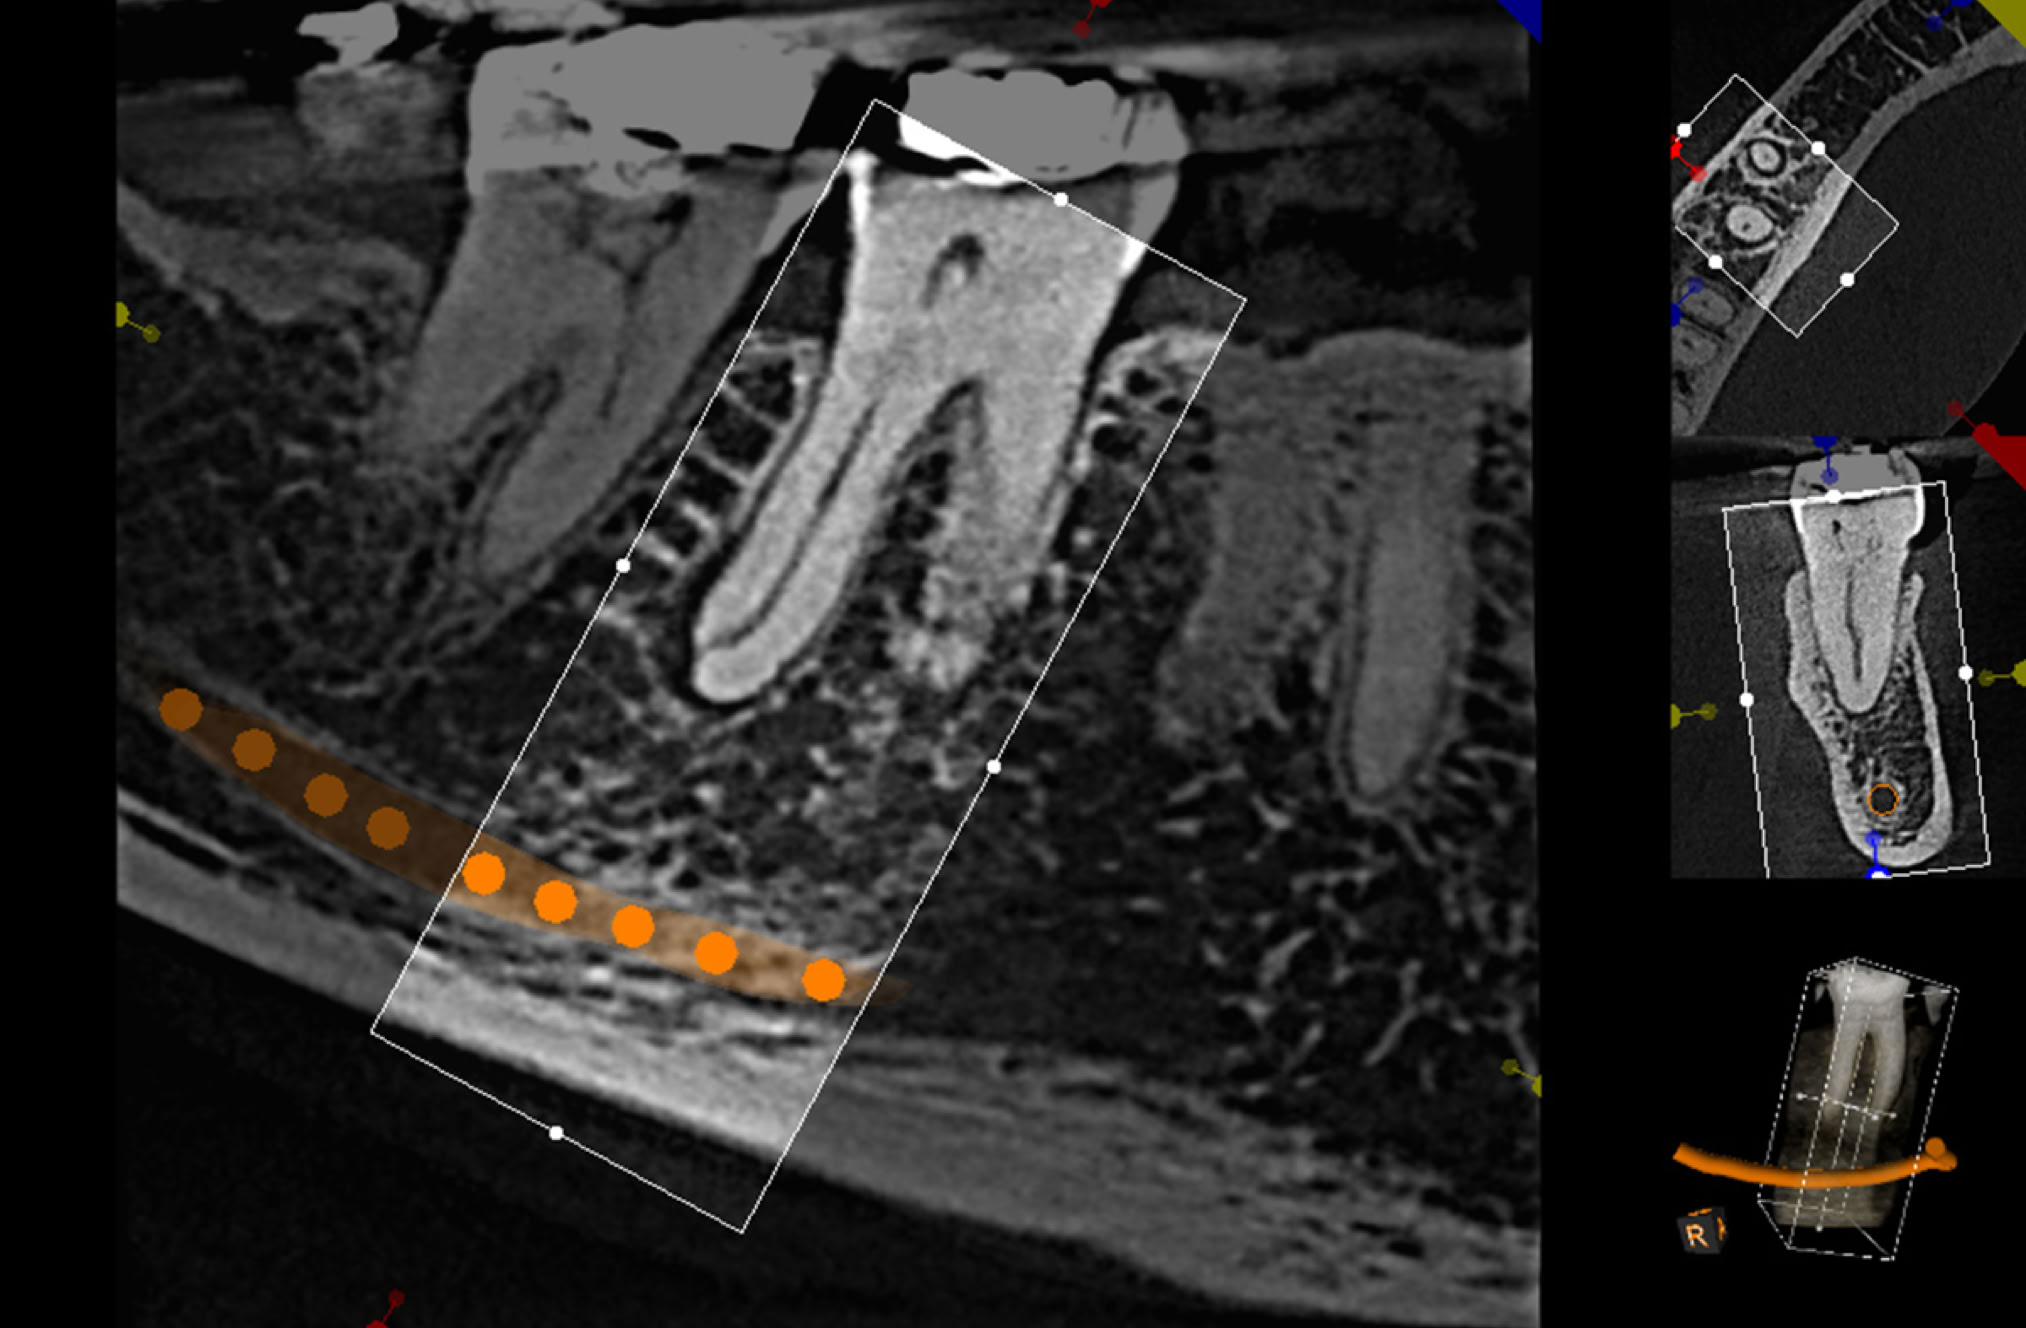

Wir finden die richtige Einstellung zur Beantwortung Ihrer Fragen.

FIELD OF VIEW

BIS ZU EINER GRÖSSE VON 17 cm x 13,5 cm

Mit der derzeit modernsten und strahlungsarmsten digitalen Aufnahmetechnik wird es möglich, eine sehr exakte röntgenonolgische Darstellung des Schädels in allen drei Dimensionen zu erhalten.